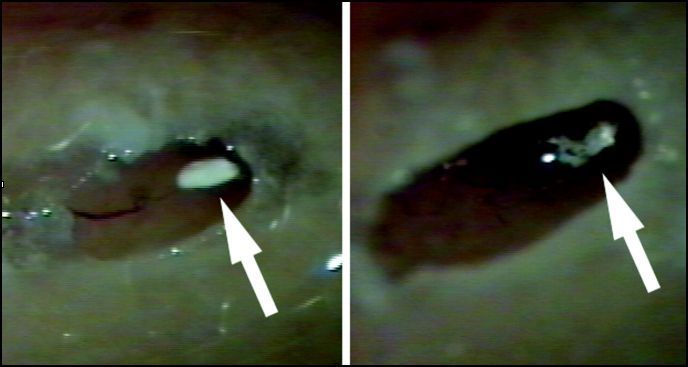

Le nystagmus est un mouvement d'oscillation involontaire et saccadé du globe oculaire. Dans le syndrome vestibulaire, la secousse lente est dirigée vers le côté

malade, puis la secousse rapide « rattrape » ce décalage, battant du côté sain. Le sens du nystagmus est donné par la secousse rapide. Il s'examine mieux à l'aide de lunettes de Frenzel, qui inhibent la fixation oculaire, cette dernière altérant la manifestation du nystagmus. On utilise plus volontiers de nos jours, des lunettes de vidéonystagmoscopie reliées par fréquences radio au capteur d'un moniteur qui donne une image "en direct" du nystagmus, bien plus élaborée que celle obtenue sous lunettes de Frenzel. En cas de difficultés diagnostiques, une vidéonystagmographie peut être proposée.